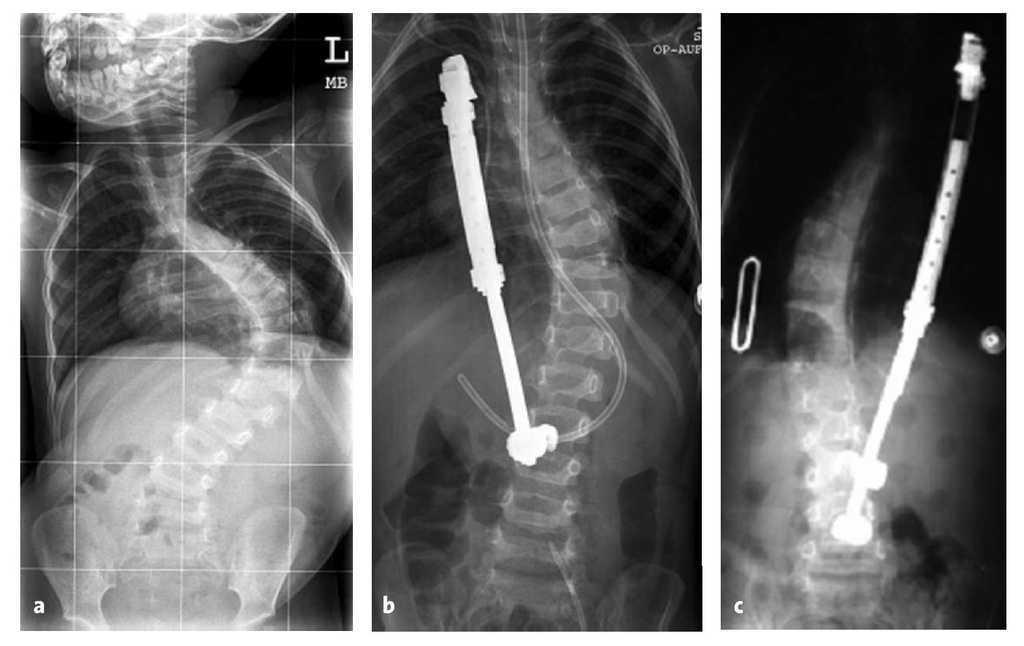

La indicación para la intervención fue en 16 casos una escoliosis congénita (figs. 24a-24c), en once casos una escoliosis neurológica y en doce casos una EIP. Las curvas se determinaron según Cobb. El ángulo de Cobb antes de la intervención medía un promedio de 65º (45-130º), y después de la intervención, un promedio de 32º (25-75º). En 18 pacientes tratamos una escoliosis torácica, en 18 pacientes una toracolumbar y en tres pacientes una lumbar (mielomeningocele). En 18 casos se utilizó un implante «costilla a costilla», en cinco casos un sistema de barra doble hasta la pelvis y en 18 casos un sistema híbrido (figs. 25 y 26).

Figuras 24a a 24c. a) Radiografía anteroposterior preoperatoria de una escoliosis congénita grave con sinostosis costales, hemivértebras, barra vertebral no segmentada y vértebra en mariposa. b) Radiografía lateral preoperatoria. c) TC tridimensional con reconstrucción. En los casos de deformidades graves puede resultar útil para la planificación de la intervención un modelo confeccionado a partir de estos datos.

Figuras 25a a 25c. a) Radiografía preoperatoria en proyección anteroposterior de una EIP con un ángulo de Cobb de 86º. b) Radiografía postoperatoria de una instrumentación «costilla a CL» realizada en una escoliosis toracolumbar progresiva. c) Radiografía postoperatoria en proyección anteroposterior después de 5 años. La curva se mantiene flexible y con buena corrección.